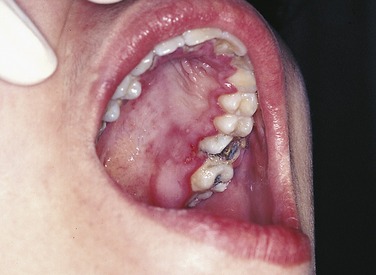

PLATE 6 Primary herpetic gingivostomatitis in an adolescent. Note the painful, swollen gingiva.